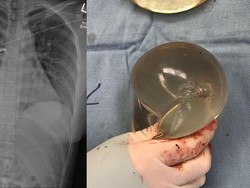

Presiden Joko Widodo (Jokowi) menyoroti banyaknya masyarakat yang berobat ke luar negeri, termasuk ibu-ibu yang melakukan operasi plastik.